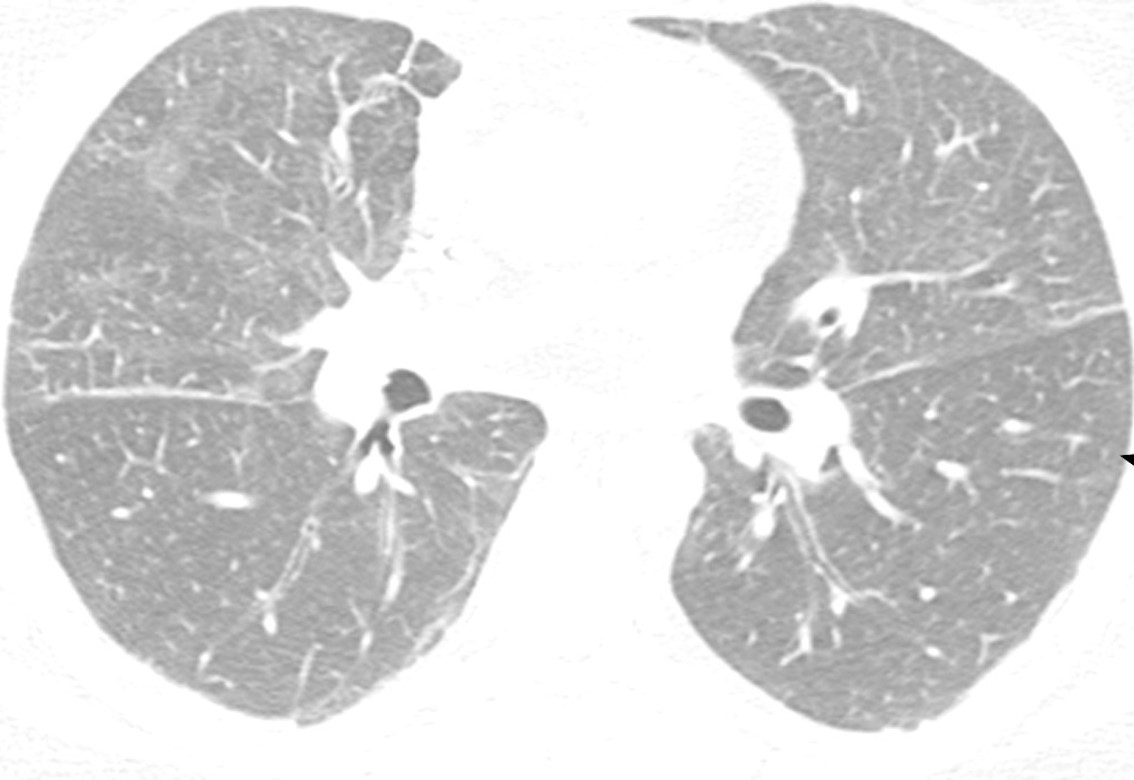

Example

Lacking honeycombing, probable UIP exhibits bronchiectasis and may have histopathologic signs of UIP upon biopsy. Surgical biopsy therefore may aid in IPF diagnosis.3

Note the lack of honeycombing in this image.

HRCT image of possible usual interstitial pneumonia. Reprinted from Fishman‘s Pulmonary Diseases and Disorders. 4th edition 2007. Meltzer EB and Noble PW: Chapter 70, Idiopathic Pulmonary Fibrosis.10 Used with permission from McGraw-Hill Companies. Inc. Copyright © 2007 McGraw-Hill Companies. Inc.